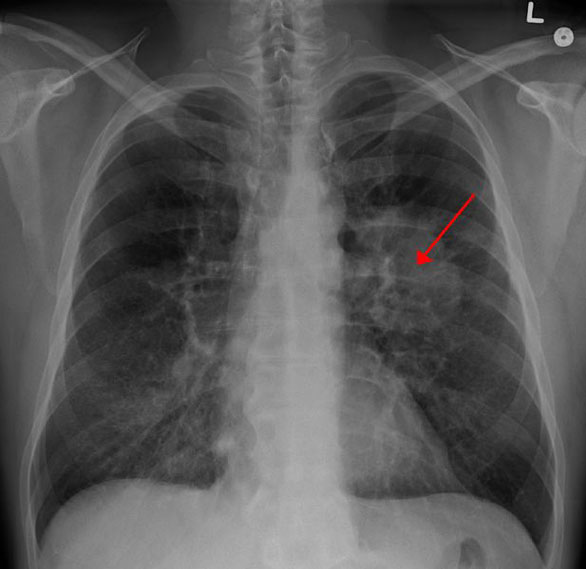

早在2013年,美國預(yù)防服務(wù)工作組就建議:年齡在55至80歲、有30年吸煙史、目前吸煙或戒煙時間不足15年的成人,應(yīng)每年做一次低劑量螺旋CT以篩查肺癌。

如果10%-100%的人在篩查時進行戒煙干預(yù),與僅篩查相比,肺癌死亡率將降低3%-52%;如果有3%-25%的人戒煙成功,患肺癌后的預(yù)期生存期要比僅進行篩查的人長40%-200%。

以1950年代出生的人為例,在篩查率為30%的情況下,在第一次篩查后采取戒煙干預(yù)措施(戒煙成功率10%)將使肺癌死亡數(shù)進一步降低14%,壽命也比僅篩查組增加了81%。